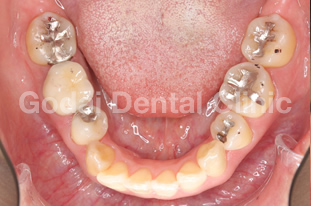

患者様は20代男性、虫歯の治療をしたいことと、歯並びを改善したいという主訴で来院されました。歯医者は10年以上ぶりですが、虫歯も歯並びもしっかり治したいという希望を持っていました。久しぶりの歯医者ということもあり、まずは歯磨きの仕方から改善していきました。歯垢をブラッシングで除去できるようになったところで、虫歯の治療を開始しました。歯並びが悪いこともあり、多くの歯に虫歯が見つかりました。患者様の年齢と歯質の保存を優先し虫歯の治療はコンポジットレジン修復を行いました。また下の親知らずが横向きに生えていたため、左右の親知らずの抜歯を矯正前に行いました。

歯ブラシの改善と虫歯の治療、親知らずの抜歯が終わったところで、矯正治療へ移行しました。患者様は健康な歯を抜きたくないという希望を持っていたので非抜歯の治療計画を立てました。まずは上下顎ともに拡大装置を用い歯列の拡大を行いました。その後、アライナーを使ったインビザライン矯正治療へ移行し、歯並びの修正と咬み合せの確立を行いました。拡大装置を使っている際は、口内炎や話しずらさなどがあったそうですが、インビザライン治療に移行してからは痛みも話しずらさもなくなり快適に過ごせたそうです。もともと多くの虫歯があったため矯正中の虫歯が心配でしたが、インビザライン矯正治療を選択したことで、新しい虫歯を作らずに治療を終えることができました。

歯並びを改善したい場合でも、歯磨きの確立、虫歯の治療、親知らずの抜歯など矯正前に治療が必要な場合もあります。ただ矯正前の治療をしっかりと行うことで、矯正治療の結果がより良いものになりますし、治療もスムーズに進みます。最終的に患者様にとって最善の治療になるよう心がけて治療を行っています。口の中が心配な方は、いつでもご相談ください。

治療前1

治療後1

治療前2

治療後2

治療前3

治療後3

治療前3

治療後3

治療前3

治療後3